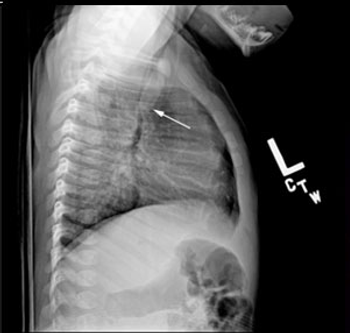

Recovery from a hemopneumothorax had progressed well for this 29-year-old man until today when he presents to the ED with dyspnea and pleuritic chest pain. What do you see on the chest x-ray?

Persistent symptoms of hemothorax or pneumothorax, in the absence of new x-ray findings require further inquiry, including chest CT, to rule out PE.